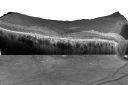

Plaquenil Toxicity - Bull's Eye Maculopathy - 25 Years Therapy - OCT Line Scan786 views73-year-old woman has been on Plaquenil for twenty five years. Plaquenil has now been stopped for 6 months. VA continues to decline as does visual function - 20/80 OD , 20/40 OS     (1 votes)

Plaquenil Toxicity - Bull's Eye Maculopathy - 25 Years Therapy OCT Line Scan971 views73-year-old woman has been on Plaquenil for twenty five years. Plaquenil has now been stopped for 6 months. VA continues to decline as does visual function - 20/80 OD , 20/40 OS     (0 votes)